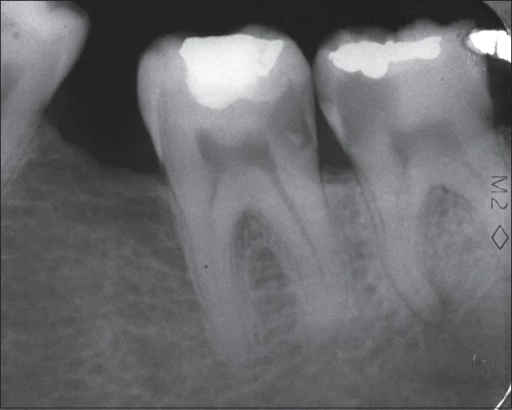

En consulta se realiza exploración clínica y, con frecuencia, se indican radiografías de aleta de mordida para visualizar el área interproximal. En fases muy tempranas, puede verse como una zona radiolúcida triangular en el esmalte.

La radiografía de aleta de mordida permite detectar lesiones interproximales incipientes.